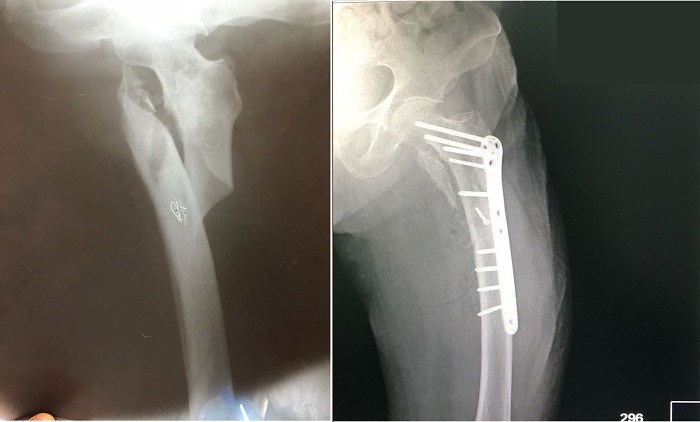

Классификация переломов диафиза бедренной кости: Иллюстрации и информация